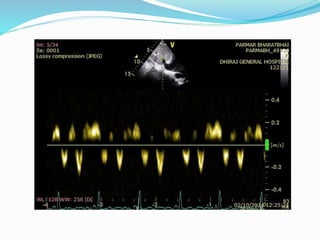

Doppler findings:

 Superior Vena Cava: Diastolic Flow Velocity > Systolic Flow

Velocity

 Hepatic vein: Exaggerated diastolic flow reversal after onset of

expiration.

 Pulmonary Venous Flow: Increase in diastolic flow velocity on

expiration. Systolic/Diastolic flow velocity ratio < .65

 Peak Diastolic flow velocity falls 40% on inspiration.

 Mitral inflow pattern: During onset of exhalation – 25%

increase in early diastolic flow velocity